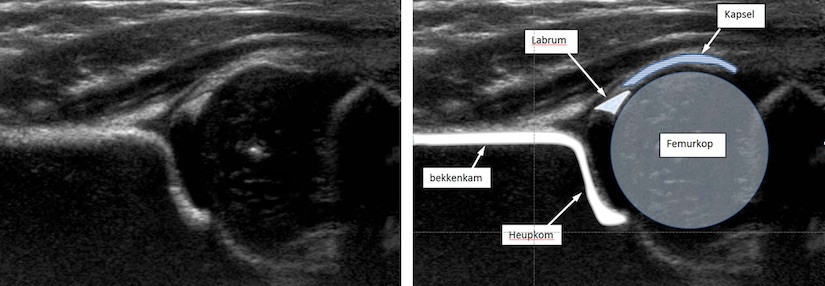

Links: een echo van een normale heup bij een kind van 3 maanden oud.

Rechts: de belangrijkste anatomische structuren die op de echo van een babyheup te zien zijn.

Het maken van een echo wordt bij baby’s onder andere gebruikt om te kijken of er sprake is van dysplastische heupontwikkeling (heupdysplasie en/of heupluxatie). De baby wordt op de zij in een speciaal kussen gelegd waarna de echoscopist de heup bekijkt met behulp van de transducer. Daarna wordt de baby op de andere zij gelegd om de andere heup te onderzoeken. Dit onderzoek is mogelijk tot de heupkop begint te verbenen. Het is afhankelijk van de ontwikkeling van de baby wanneer dat precies is, maar meestal is dat rond de leeftijd van negen maanden.